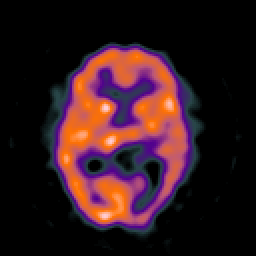

SPECT TC Study #8 -- Slice #28

[Home][Help][Clinical][Tour 1][Tour 2][Tour 3] Slice 28